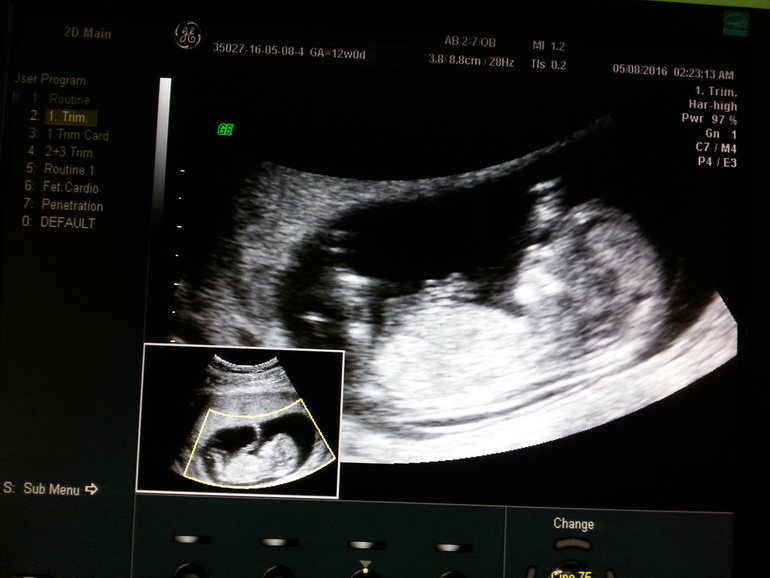

Теперь немного по цифрам)

Срок по М 12+1

КТР 63 мм

ЧСС 154 уд/мин

ТВП 1,8 мм

Носовая кость 1,9 мм

По КТР плода беременность 12+5

В этот раз после осмотра попросила узистку, чтобы она мне выбрала ракурс и я смогла сфотографировать малыша на экране, так что выкладываю фото. Сверху-это то, что видела я, а снизу то, что видела врач на мониторе) Кстати предположили девочку, но я пока не хочу акцентировать на этом внимание, ведь для меня самое главное, чтобы малыш рос и родился здоровым